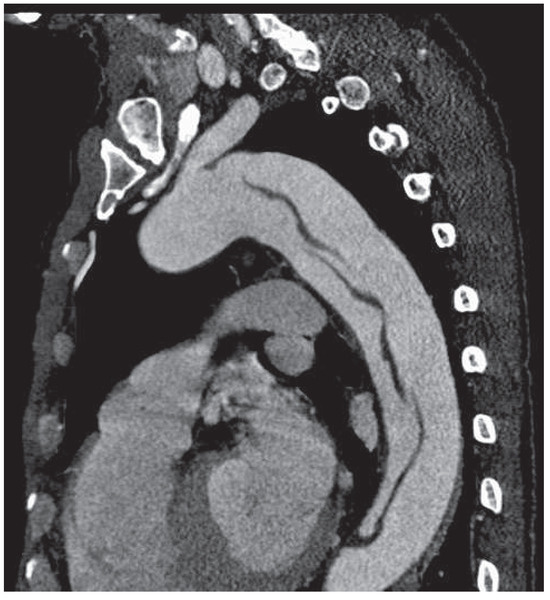

Endovascular Treatment of a Complex Type B Aortic Dissection

by Wen-Dong Li, Qing-You Meng, Li-Wei Zhu, Wen-Bin Wang, Ye-Qing Zhang, Cheng-Long Li and Xiao-Qiang Li

Aortic dissection is a rare disease with high morbidity and mortality, especially when involving multiorgan malperfusion such as lower extremity and visceral ischaemia. Revascularisation should be performed to restore perfusion immediately. We report a case of acute Stanford type B aortic dissection complicated [...] Read more.

Aortic dissection is a rare disease with high morbidity and mortality, especially when involving multiorgan malperfusion such as lower extremity and visceral ischaemia. Revascularisation should be performed to restore perfusion immediately. We report a case of acute Stanford type B aortic dissection complicated by lower extremity, renal and superior mesenteric ischaemia. The right iliac artery was occluded because of compression of the false lumen, resulting in thrombosis. The patient was successfully treated with endovascular treatments, including thrombus extraction and iliac artery, superior mesentic artery and aortic stenting combined with fenestration. Full article